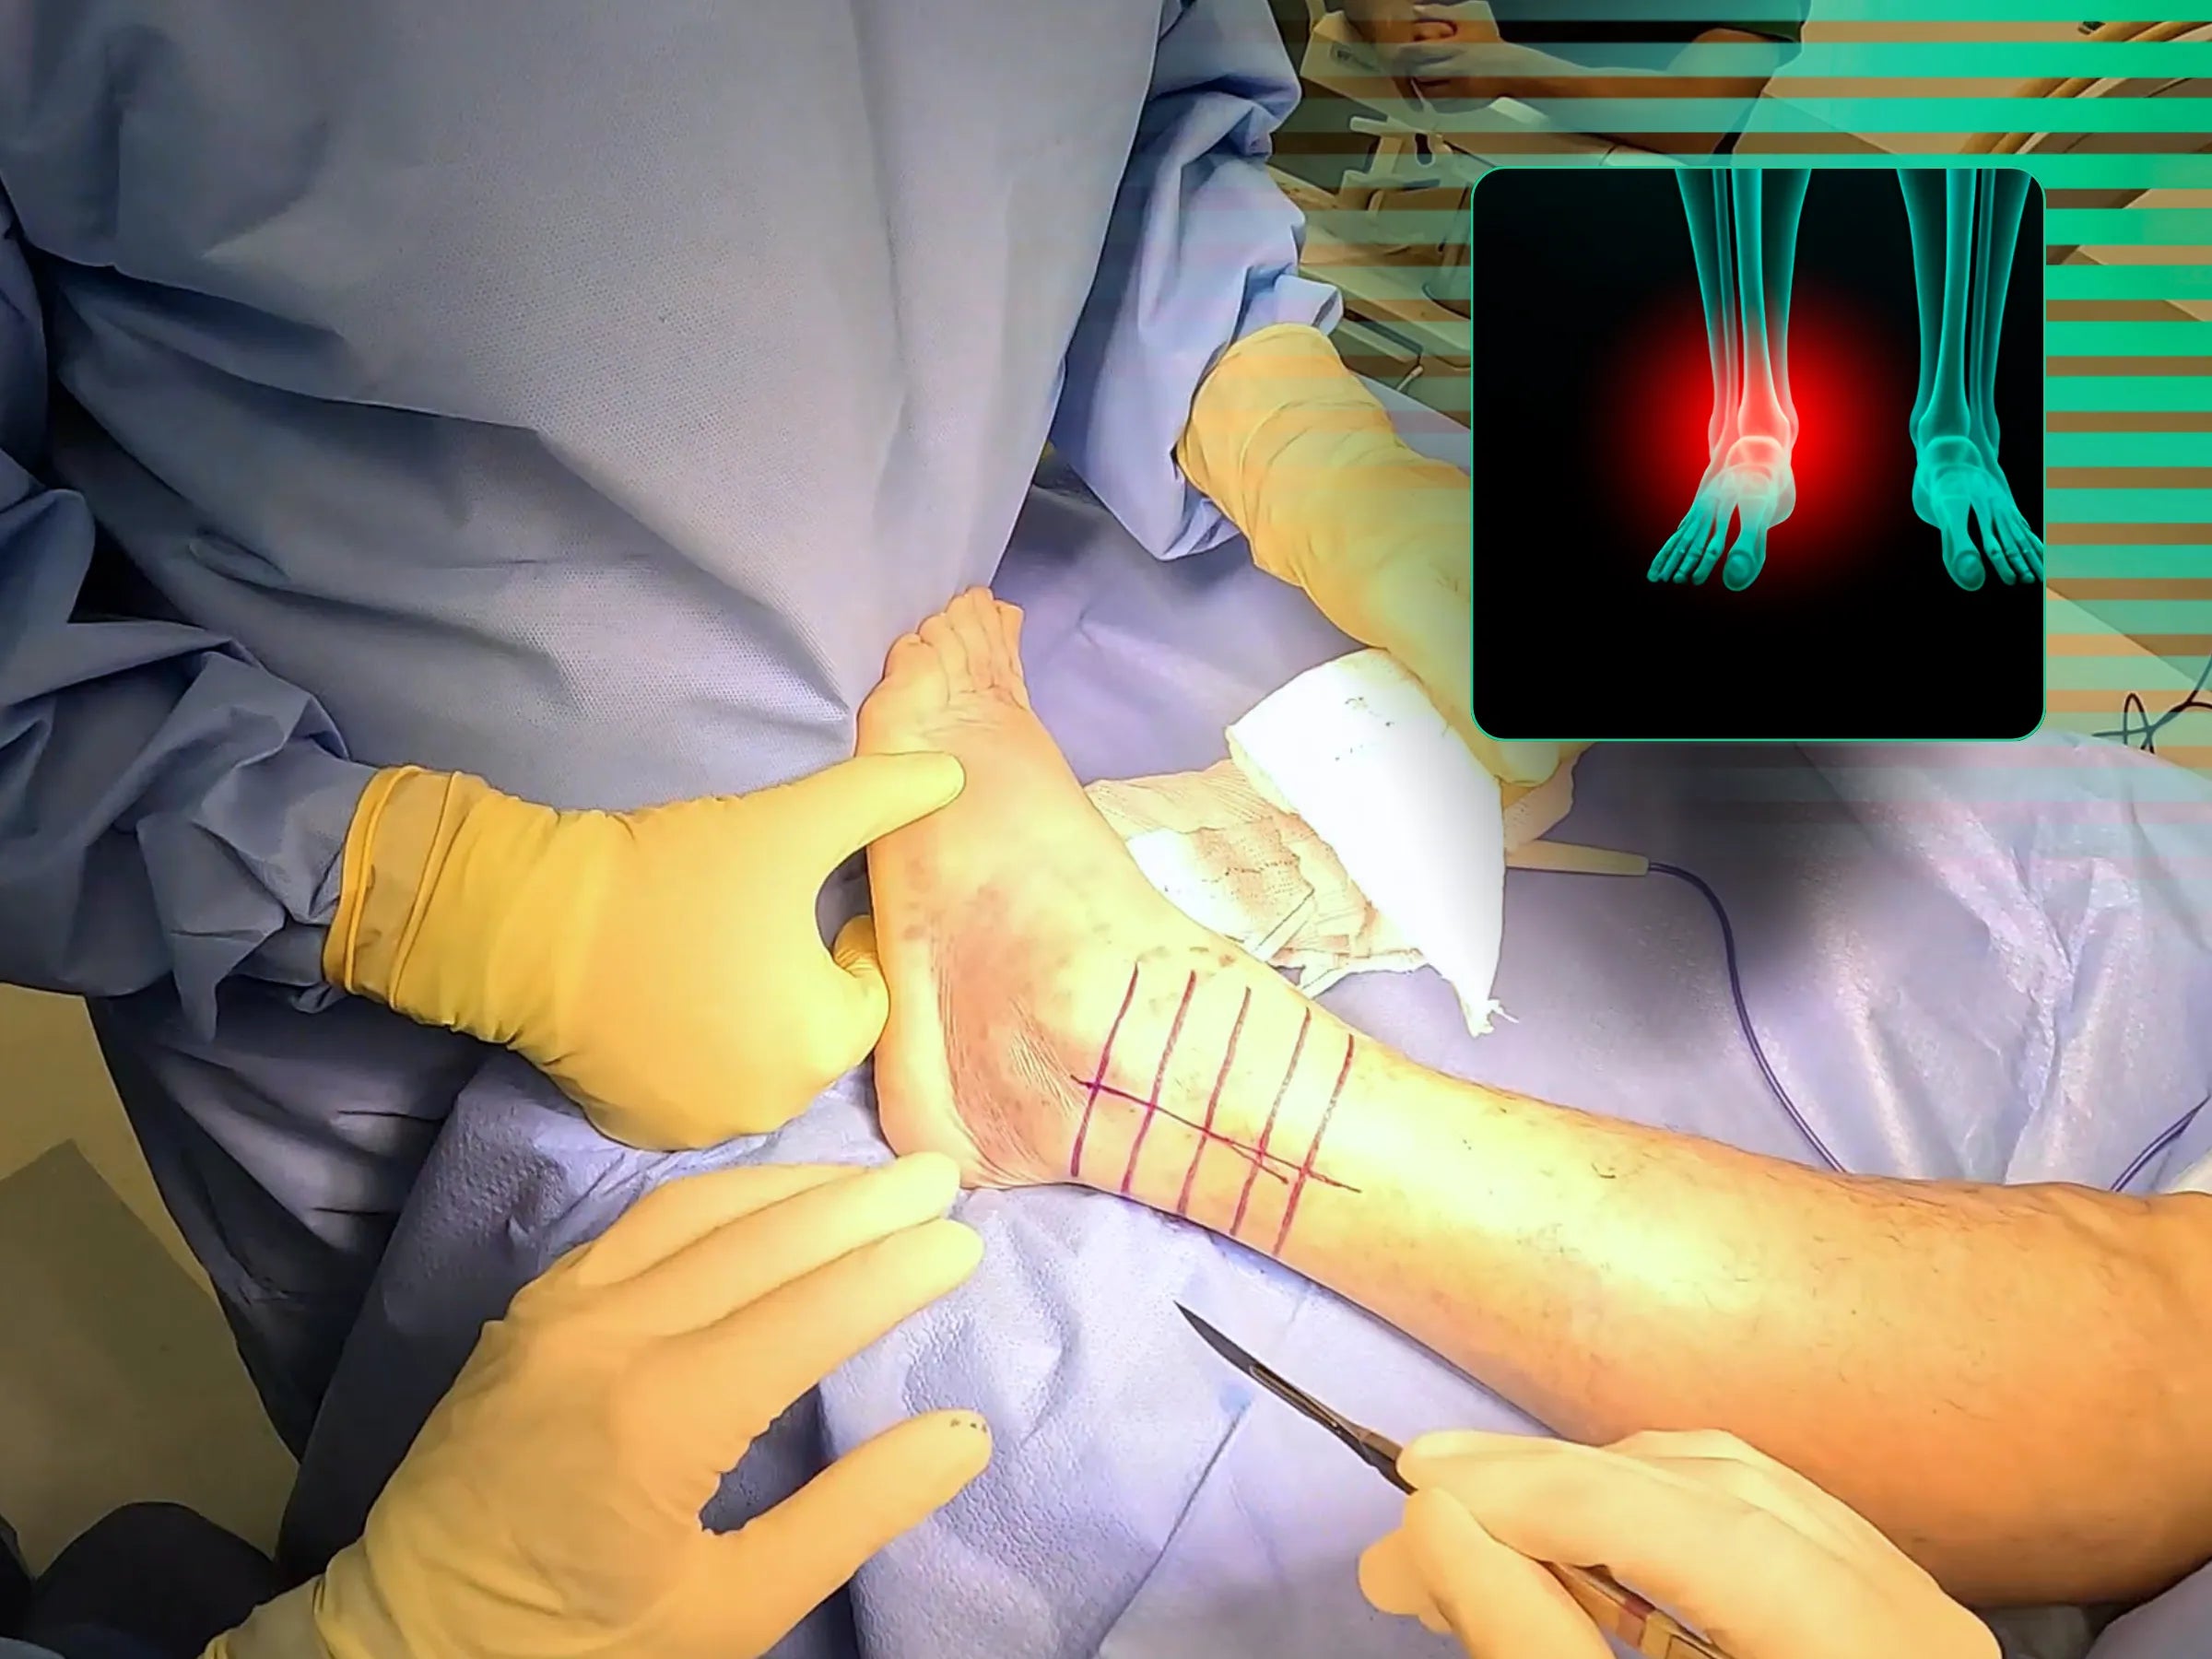

- Fechamento Cirúrgico Otimizado: Protocolo de fechamento por planos, seguindo marcações dermográficas para um resultado estético favorável.

- Técnica de fixação do fragmento de Wagstaffe com parafusos de dupla compressão.

- Fixação Estratégica do Fragmento de Wagstaffe: Abordagem detalhada para fixação do fragmento com dois parafusos de dupla compressão, visando a estabilização anterolateral da sindesmose.